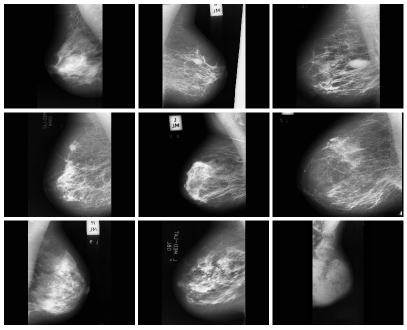

In the present study, we conducted our experiments using the images from the MIAS dataset DatasetMIAS15 . This dataset contains 322 mammography images (119 of which are abnormal images and the rest are normal). All mammograms are taken in a Medio-lateral oblique, with the dimension of 1024*1024 a resolution of 200. Several samples of this dataset are shown in Fig. 3.

The radius of the smallest mass in this database is 3 m pixel and the one for the biggest mass equals 197 pixel. This dataset is also divided into 7 different categories.

Refer to caption

Figure 3: Examples from the MIAS dataset. In this dataset, the pectoral muscle and out-layer objects make the segmentation a challenging task. Therefore, in this paper we propose several techniques to improve images before segmentation.